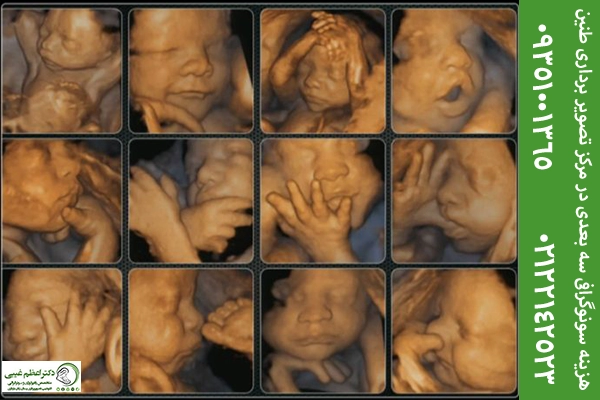

۶. سونوگرافی سهبعدی و چهاربعدی: سونوگرافیهای سهبعدی و چهاربعدی بیشتر جنبهی تصویری دارند و برای دیدن چهره و حرکات جنین استفاده میشوند.

برخی مراکز از دستگاههای تصویربرداری سهبعدی و چهاربعدی استفاده میکنند که تصاویر واضحتر و دقیقتری از جنین ارائه میدهد. این تجهیزات گران قیمت موجب افزایش هزینه سونوگرافی خواهند شد.

| سونوگرافی سهبعدی و چهاربعدی | مشاهده چهره و حرکات جنین با جزئیات بیشتر؛ بیشتر جنبه زیبایی و تصویری دارد | ۱,۵۰۰,۰۰۰ تا ۲,۰۰۰,۰۰۰ |